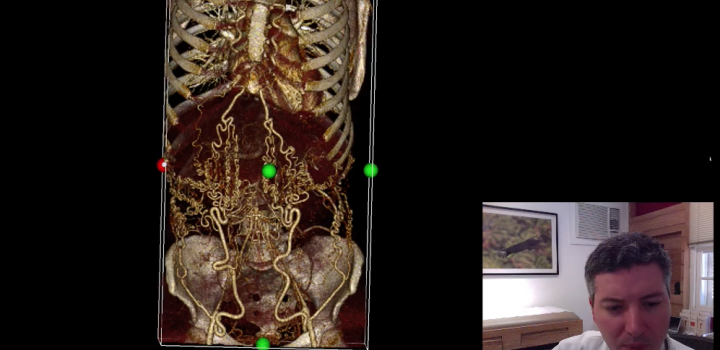

- 3D Volume Rendering

- EVAR Planning (plugin)